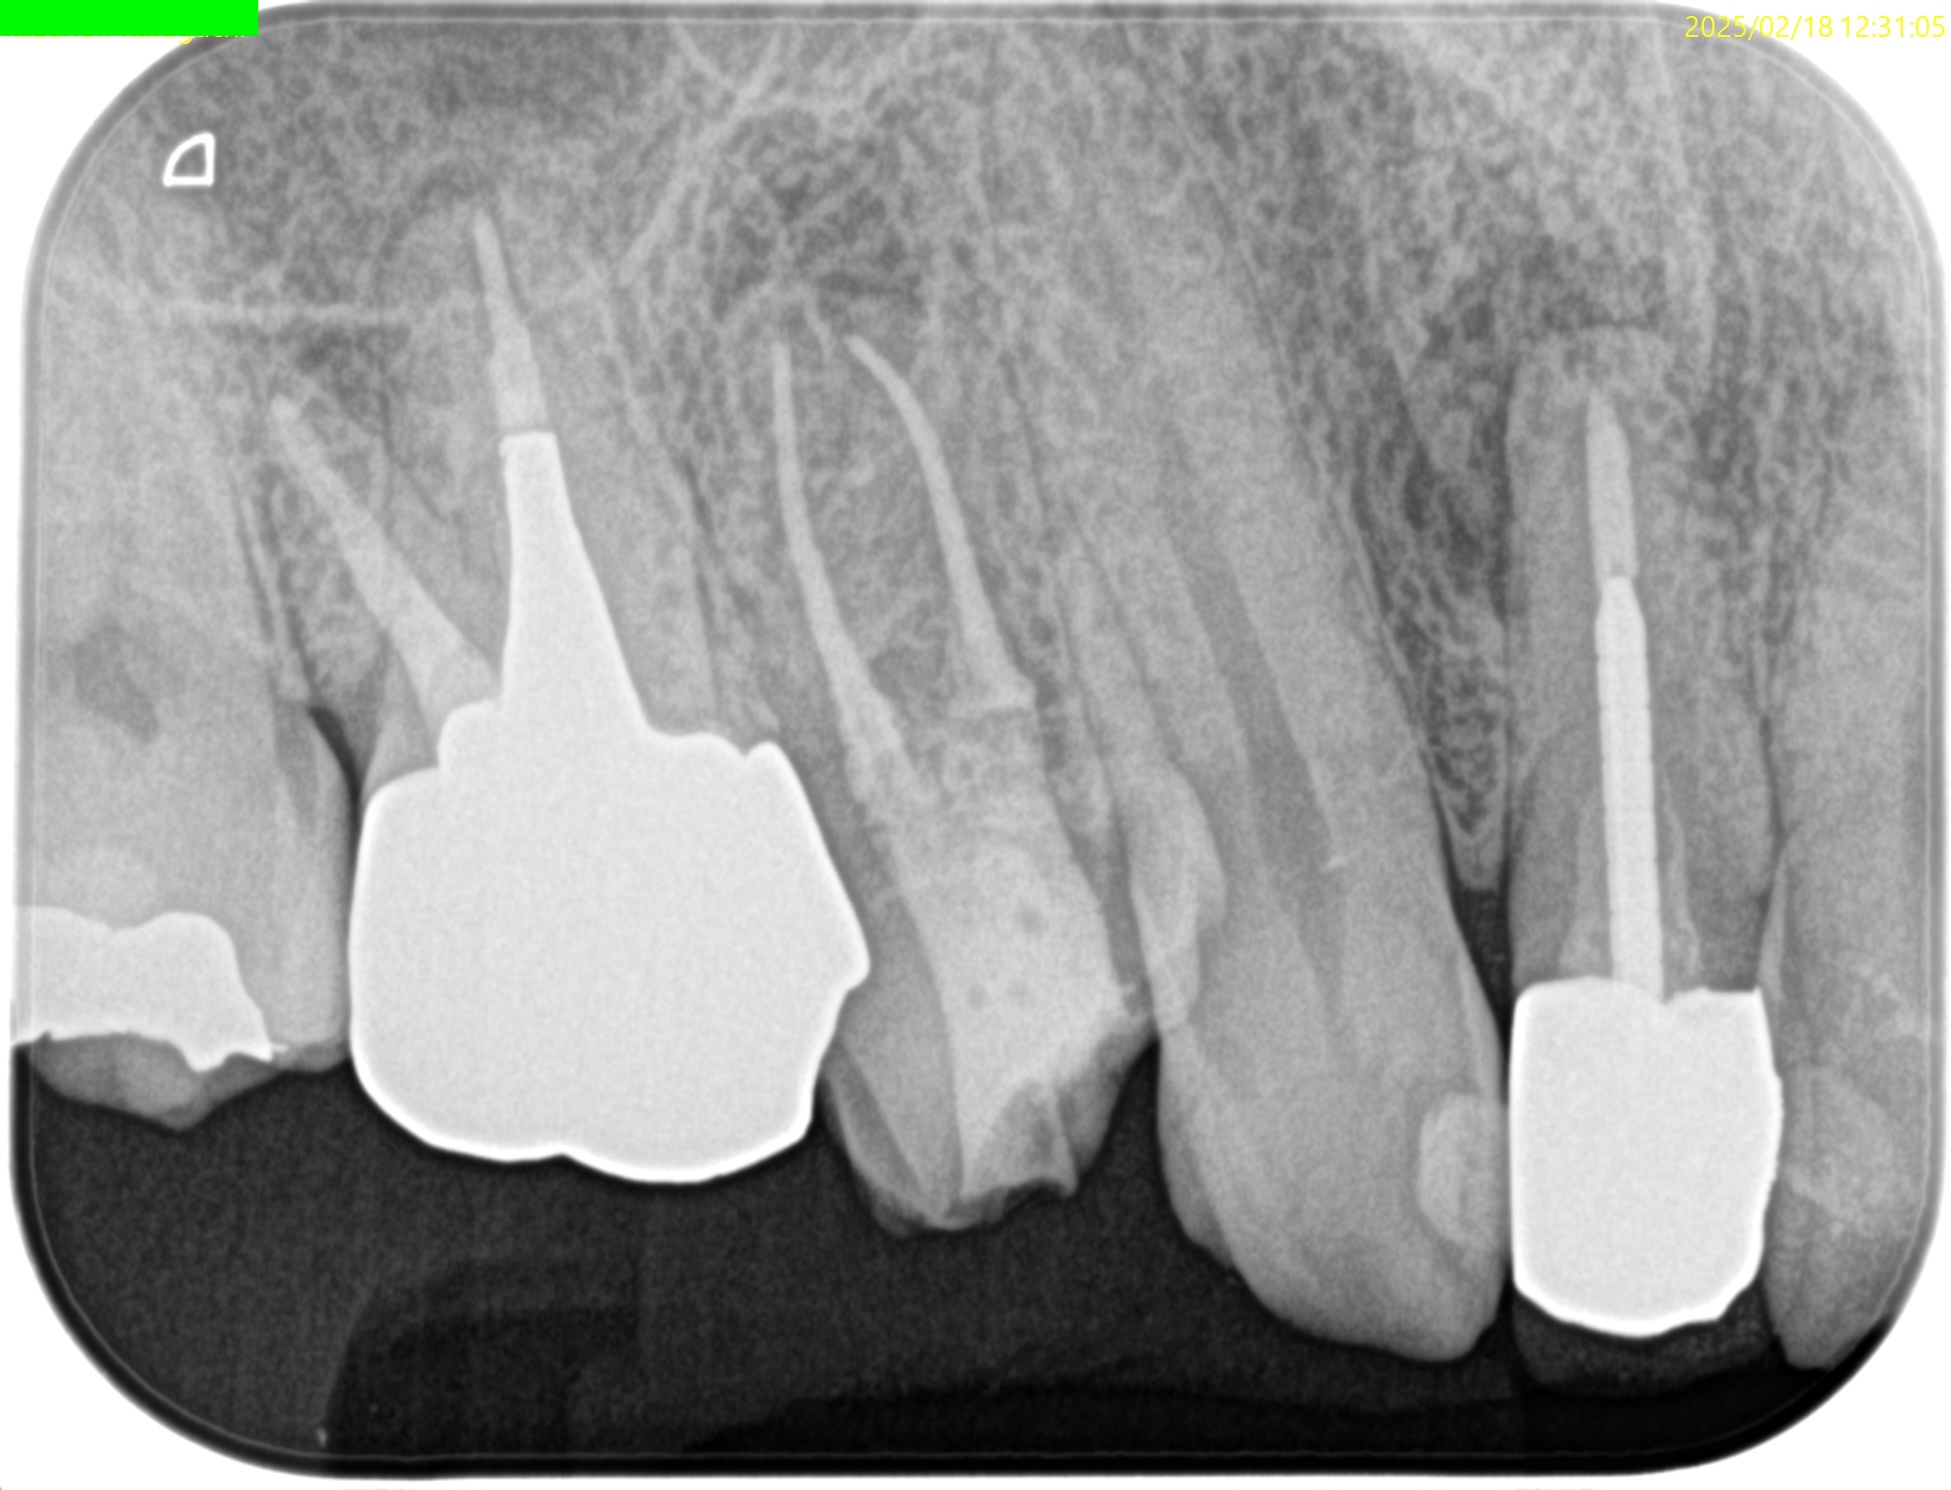

Pre-op Endo test(2025.2.18)

#3

MB

DB

P

まず、#3 Pのみ再根管治療を行い(2025.2.18)、